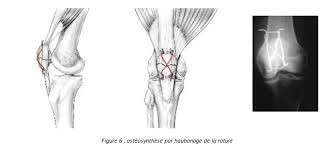

Ci après quelques illustrations de traitement chirurgical :

Brochage Haubange de rotule